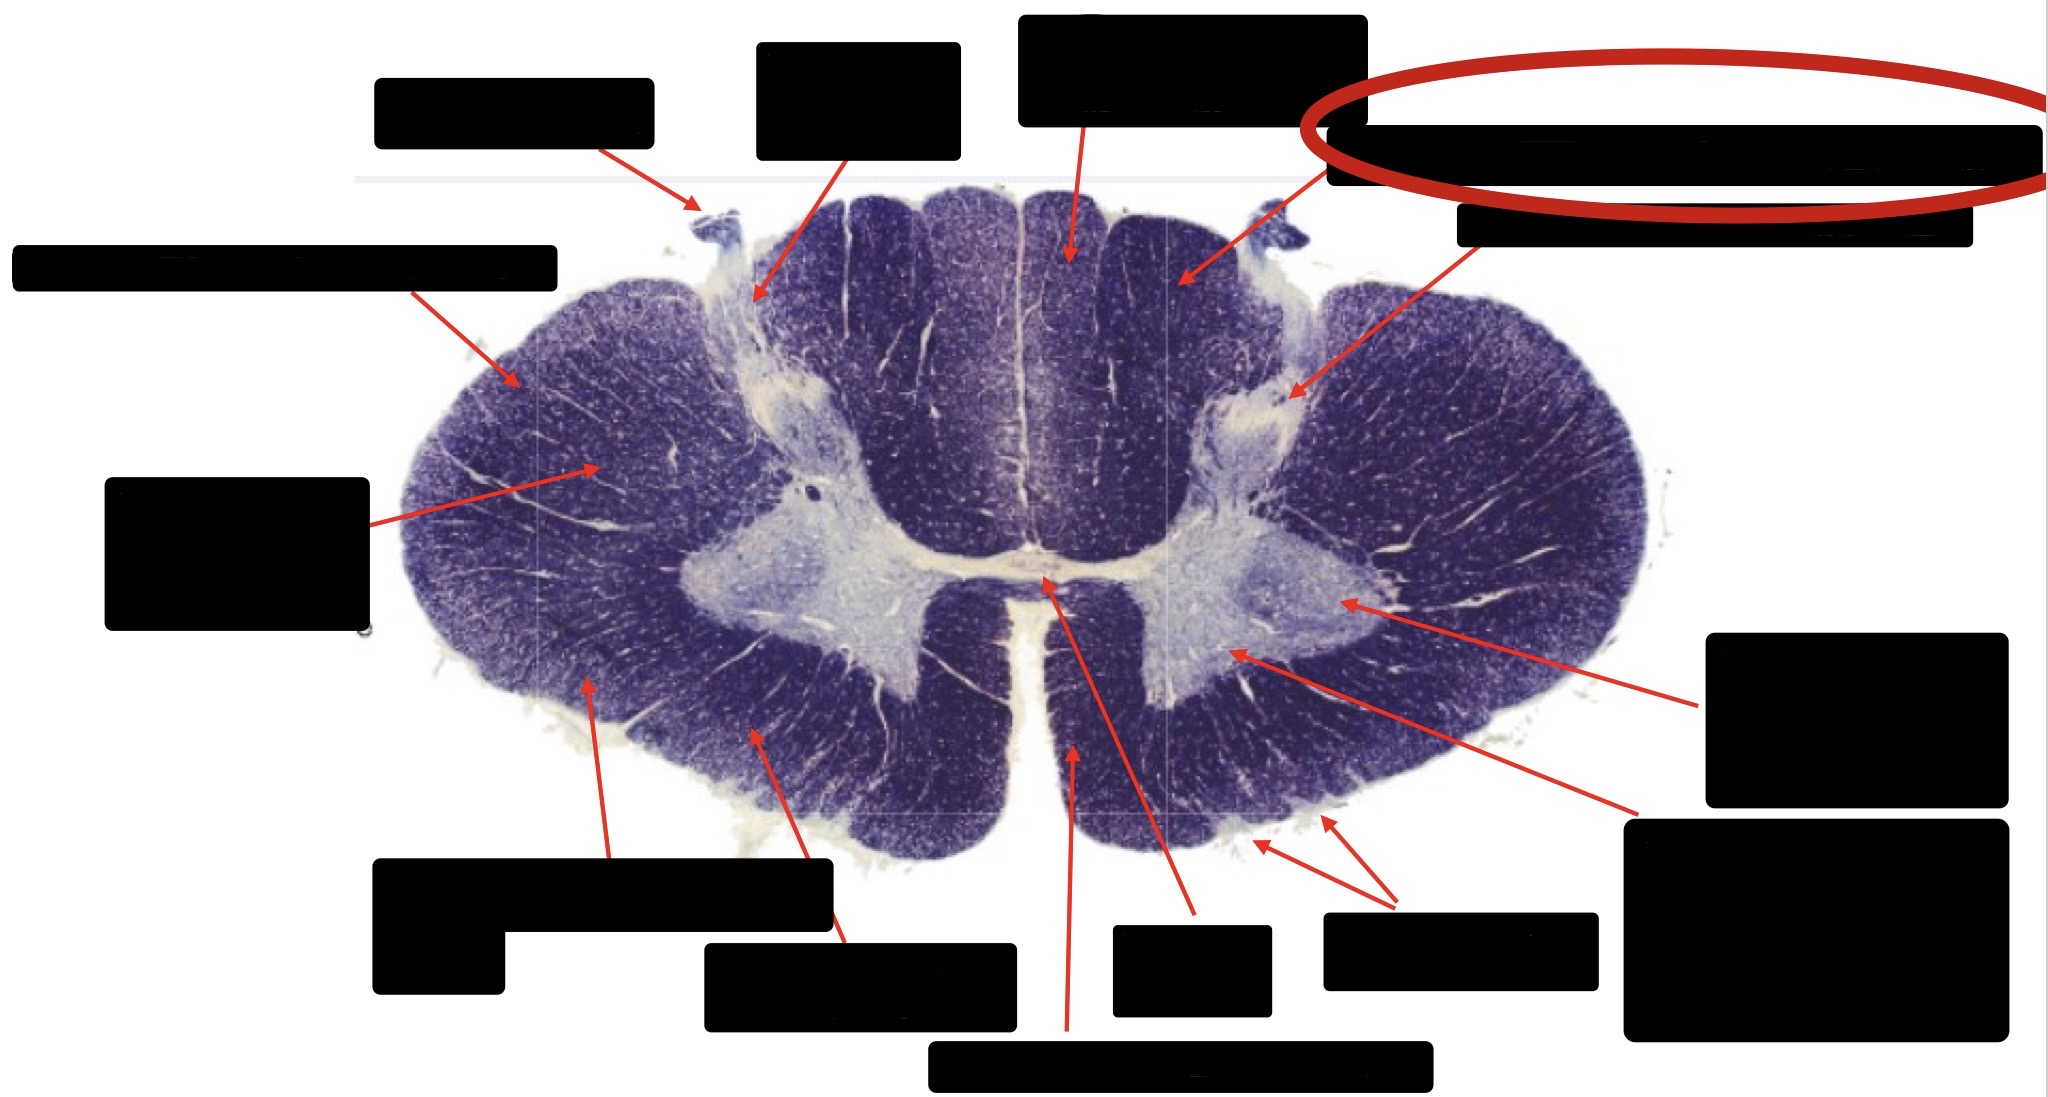

Anterior Spinal Artery

Denticulate Ligament

Ventral Root

Dorsal Root

Posterior Column Fasciculus Gracilis

Large Fiber Entry Zone

Central Canal

Dorsal Rootlet

Lissaeur’s Tract & Small Fiber Entry Zone

Substantia Gelatinosa

Lateral Corticospinal Tract

Anterior Horn Motor Neuron

Spinothalmic Tract

Anterior Horn Motor Neurons